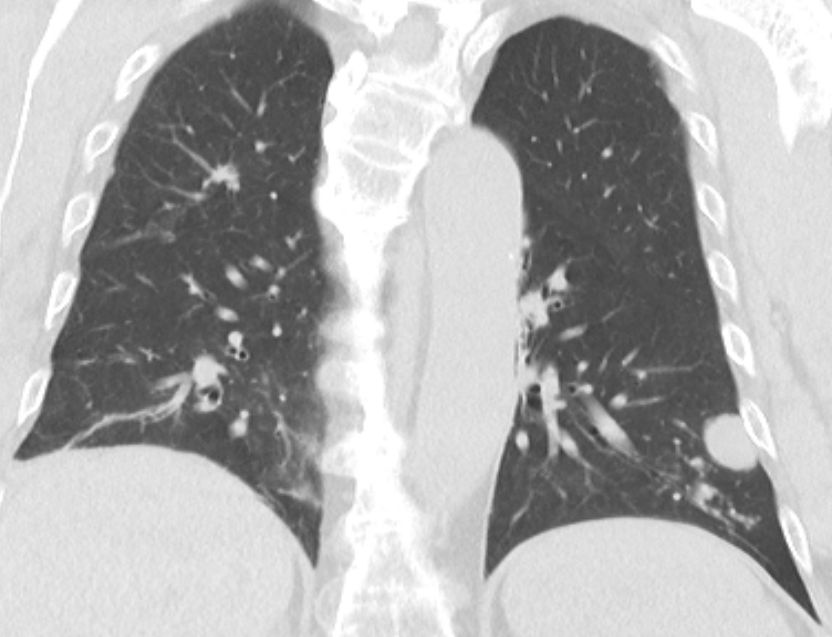

Lungenmetastasen 66-jähriger Mann mit stenosierendem Karzinom der Fexura coli dextra. Lymphknotenmetastasen. 2 Lungenmetastasen.